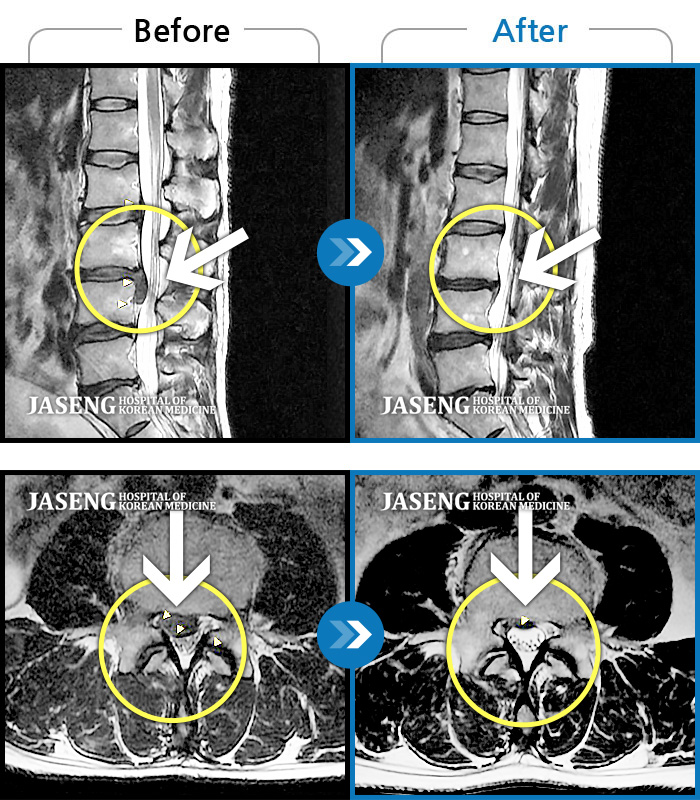

허리디스크

해운대 · 이상건 원장

허리통증, 좌측 다리 저림 및 근력 저하

촬영시기

2017.09.08 ~ 2018.05.11

2019.01.04

조회수 4,033